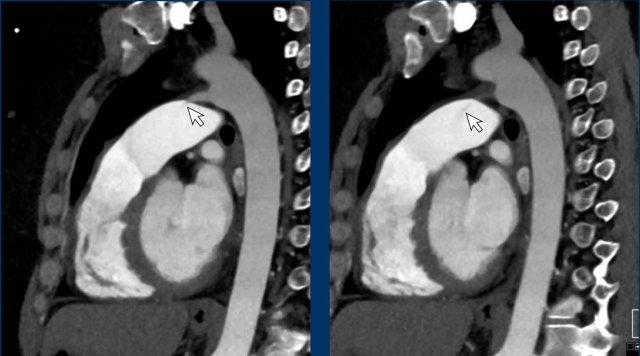

Hình ảnh

PAPVR bên trái phát hiện tình cờ với dẫn lưu trên tim của máu từ thùy trên trái vào tĩnh mạch tay đầu trái (các mũi tên).